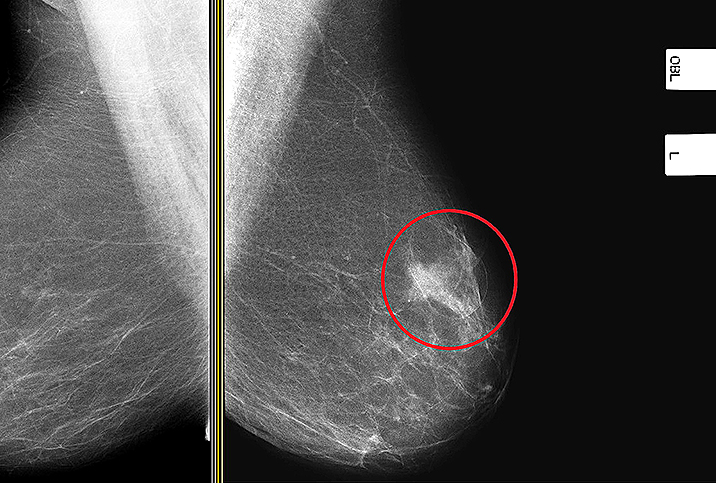

A mammogram is an X-ray picture of a patient’s breasts that is reviewed by medical staff and used during cancer screening. Together with monthly breast self-examinations and regular clinical exams, mammograms play a crucial role in the early detection and diagnosis of breast cancer.

One way mammograms save lives is through early breast cancer detection. Physicians use mammograms to detect cancer during its early stages, before the patient may even feel a lump. If breast cancer is detected early, especially at a localized stage, a patient’s survival rate is up to 98 percent. If the disease is not diagnosed and addressed early, the five-year survival rate might drop to just 25 percent.

Each of your breasts will be compressed between two surfaces to spread out the inner tissue, and then you’ll be asked to hold your breath for a few seconds while an X-ray captures black-and-white images of your breast tissue. Though you might feel some slight discomfort from pressure on your breast, this is usually very brief. The process is repeated for the other breast, and the entire procedure takes no more than 20 minutes.

The X-rays will be read by a radiologist—a physician who is an expert at reading diagnostic images—who will check for any irregularities. The radiologist will compare the current images to images from previous years, if this is not your first mammogram. Extra images that show different views of the breast tissue may be required, but don’t let this be a cause of panic or upset, because it happens frequently.

Besides X-rays, which store the images on film, a digital mammogram might be an option. Also called full-field digital mammography (FFDM), a digital mammogram produces images on a computer screen that can be enhanced and magnified for closer viewing. The images can also be downloaded to a computer application for further study.